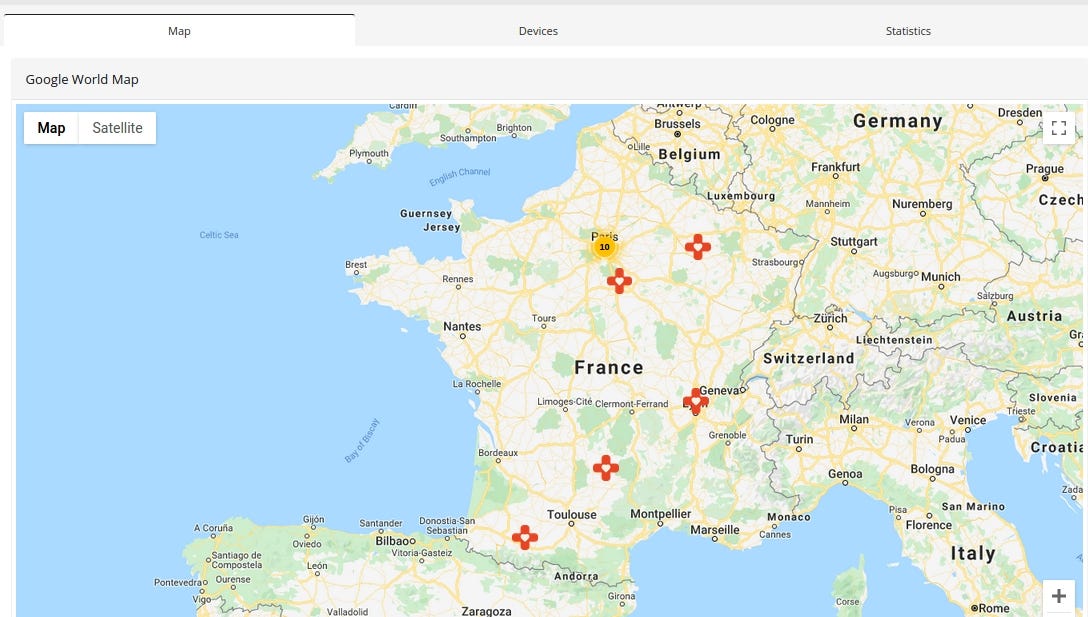

Case #2 IRM CHARENTON ST MAURICE, 22 rue Victor HUGO 94220, CHARENTON LE PONT

Medecon Clipper is web server designed to make images and reports available for the general practitioners or the specialists.

Query: http.favicon.hash:-897903496

Some devices/EMRs/software are used only in specific countries. Medecom (http://www.medecom.fr/) is a French based company and most of it are exposed in France.

Medcon Clipper reveals precise location in HTML content

IP location points to Montmorency but the actual clinic is located in suburbs of France

In addition, it shows the current version of software — 4.4. The newest one is 4.10, so it hasn’t been updated for a while.